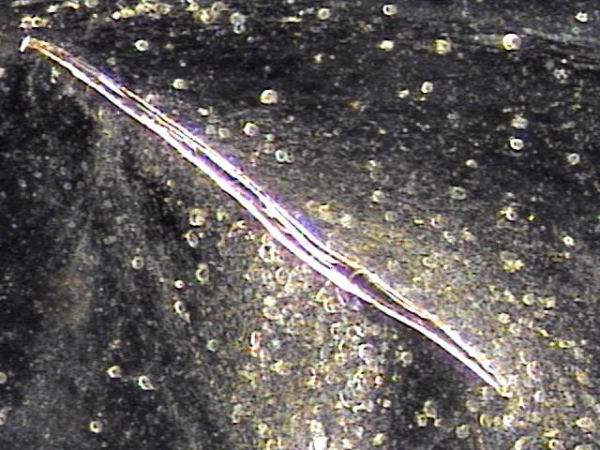

내원 첫날 전립선의 표적 치료후 치료된 정낭의 혈정액과 정자들과 염증들의 현미경학적 자료입니다.

This is a microscopic image taken after your first targeted prostate treatment, showing improvement in the seminal vesicle.

The blood-tinged fluid (hematospermia), sperm, and inflammatory cells have been successfully treated.